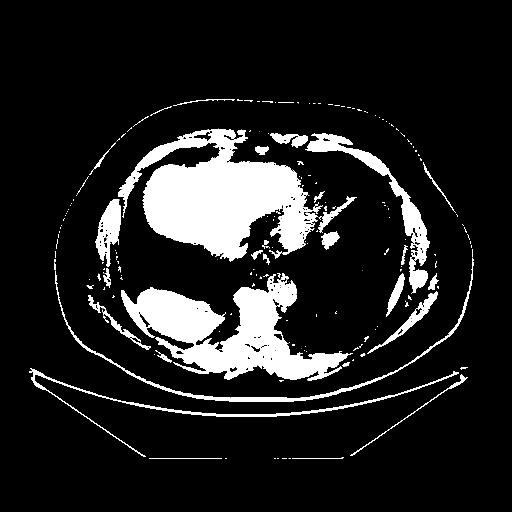

Original VENOUS CT scan

Full window (WL 1023.5, WW 4095 β†’ Low βˆ’1024, High +3071)

Actual HU range: [-1024.0, 3071.0]